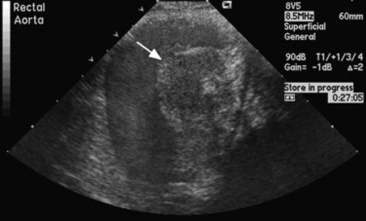

Aneurysms or pseudoaneurysms may be visualized radiographically as soft-tissue density masses continuous with a vessel wall (true aneurysm) or extending outward from a vessel wall (false aneurysm).203,204 However, the majority of the aneurysms involving the aorta and aortic root are not visible radiographically. Echocardiography is useful in the diagnosis of aneurysms involving the aortic root (Fig. 30-26).206-209 Angiography can be used in the diagnosis of peripheral vessel swelling or suspected thrombosis but is of little use in diagnosis of aneurysms of major vessels in adult animals. Ultrasonography may be used for the diagnosis of aneurysms or thrombosis of major arteries and peripheral vessels. In aortoiliac thrombosis of horses, ultrasound has been used to determine the origin of the thrombus and the extent of occlusion of the involved arteries (Fig. 30-27).218 Abdominal ultrasonography of the upper left flank dorsal to the left kidney has been used to diagnose aortoiliac thrombosis in calves.215 Diagnostic ultrasound has been used to detect thrombi in the caudal vena cava in cattle.219,220 Although the occluding thrombus is not imaged, the detection of a distended oval or round caudal vena cava, rather than the normal triangular vessel, in the eleventh and twelfth intercostal spaces is consistent with this diagnosis in cattle. Thrombi have been detected ultrasonographically in the hindlimb in both horses and cattle.221-224 Jugular vein thrombophlebitis has also been diagnosed ultrasonographically in both horses and cattle (Fig. 30-28).225,226 Similarly, diagnostic ultrasound has been used to image the cranial mesenteric artery, its branches, and the aorta in horses with verminous arteritis.227 Aneurysms appear as dilated vascular structures or vascular outpouchings continuous with the vessel wall,205 whereas a thrombus is apparent as a hypoechoic to echogenic mass within a blood vessel.226 Cavitation of an occlusive thrombus is suggestive of septic thrombophlebitis (see Fig. 30-28), whereas a nonseptic thrombus usually has a homogeneously hypoechoic to echoic appearance.226 Complete occlusion of the vessel can be determined ultrasonographically, or flow within an aneurysm or alongside a thrombus determined. Doppler ultrasound provides a more sophisticated method for determining blood flow and vessel patency. Computer-assisted radiographic techniques such as computed tomography and digital subtraction angiography may also be useful but have not yet been widely used in large animals. The latter methods may be limited in usefulness by the size of large animals and the cost of the equipment and procedures.

Fig. 30-27 Transverse sonogram of a large somewhat heterogeneous thrombus (arrow) in the terminal portion of the aorta extending into the right internal and external iliac arteries.

image